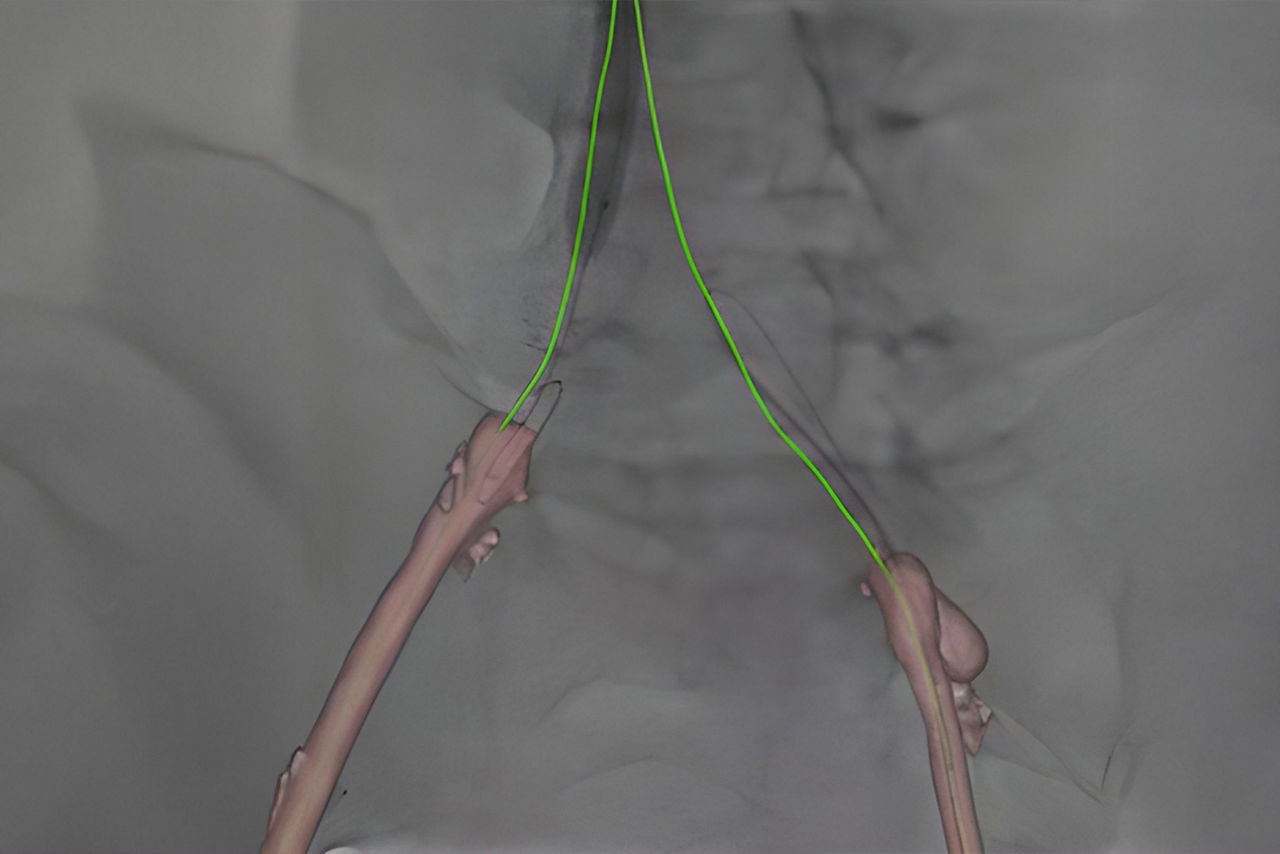

Vessel assist for neurointerventional

Vessel ASSIST delivers accurate and easy anatomy segmentation and accurate vessel quantification from 3D volumes. It also offers advanced 3D roadmap and augmented image guidance capabilities on frontal or lateral planes to guide catheter with confidence for procedure such as Aneurysm Treatment with Flow Diverter.

Plan

Segment and size the anatomy of interest in CBCT.1 Plan the stent positioning on the 3D model and prepare 3D landmarks to help guide the deployment.

Guide

Import segmented anatomy, centerline and landmarks and overlay them on live fluoroscopy on the frontal or lateral plane for 3D fusion guidance.